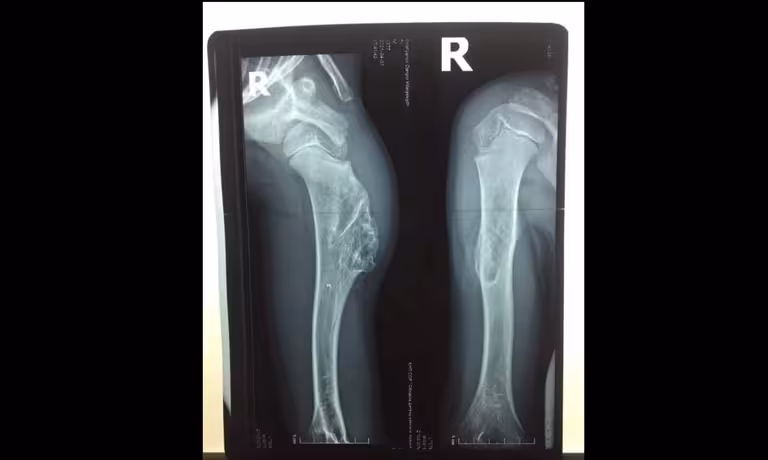

Львівські лікарі врятували руку 7-річному хлопчику (фото)

У Львівській Обласній Дитячій Клінічній лікарні «Охматдит» провели успішну операцію по видаленню пухлини у 7-річного хлопчика. Про це розповіли у пресслужбі лікарні.

Лікарі-ортопеди «ОХМАТДИТУ» прийняли важливе рішення — видаляти велику остеохондрому плеча. Маленький пацієнт ходив з нею 3 роки.

Вперше пухлину кістки у дитини діагностували у 4 рочки, але тоді лікарі прийняли рішення спостерігати, як вона себе поводитиме.

Але остеохондрома — хоч і доброякісне утворення, але все ж небезпечне, адже з часом може уражати зони росту кістки, порушувати функцію руки, кровообіг і навіть перероджуватися у злоякісну.

«Складність операції полягала у доступі до пухлини — нам треба було обійти великі судини і нерви, максимально зберегти кістку з мінімальною крововтратою, уникнути руйнування м’язів, нервових волокон і зберегти дитині функцію руки. Усе заплановане нам вдалося завдяки злагодженим діям усієї команди», — розповіла завідувачка ортопедичним відділенням Злата Кузьо.